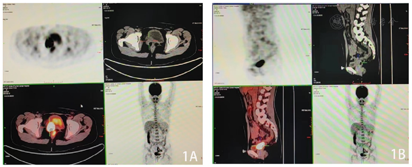

⑴阴道残端增厚并右侧肿块,大小约3.1 cm×2.6 cm,边界欠清,呈长T1长T2信号,扩散加权显著高信号,增强不均匀强化,病灶与临近膀胱及直肠分界尚清,考虑复发可能;⑵右侧髂血管旁囊性结节,大小约2.0 cm×1.4 cm;⑶膀胱、直肠未见确切异常信号。

阴道残端肿瘤穿刺活检病理:(阴道壁残端肿块)恶性肿瘤,结合病史,考虑为宫颈癌复发。免疫组化结果:CK(+),Vim(-),Ki-67(+,约60%),L-CK(+),CK5/6(-),Syn(弱+),CgA(-),P63(-)。(阴道壁残端肿块)免疫组化提示低分化腺癌,伴神经内分泌分化(图3)。